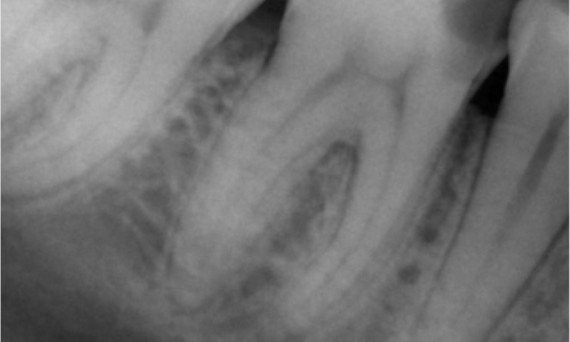

Before: Periapical radiolucency associated primarily with the distal root and loss of lamina dura on the mesial root.

After: TruNatomy was chosen in this case to allow a caries leveraged approach and a focus on pericervical dentin preservation especially on the mesial aspect where the tooth had a more minimal restoration.